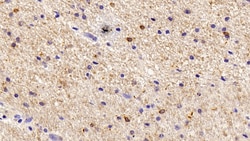

IBA1 Polyclonal Antibody for Western Blot, IHC (P)

Ionized calcium-binding adapter molecule 1 (IBA1), also known by its gene name AIF1, is a protein expressed predominantly by microglia in the brain and spinal cord. This protein belongs to the EF-hand calcium-binding protein family and plays a crucial role in microglial activation and migration in response to brain injury or neuroinflammation. IBA1's function is integral to microglial motility and phagocytic activity, facilitating the cellular response to pathogenic stimuli and promoting tissue homeostasis and repair in the central nervous system. IBA1 serves as a reliable marker for activated microglia in various neurological disorders, including Alzheimer's disease, Parkinson's disease, and multiple sclerosis, where increased expression correlates with disease progression and severity. The protein's structural features enable it to bind calcium ions, inducing conformational changes that activate signaling pathways essential for microglial function. Its expression is highly regulated by inflammatory cytokines, underpinning its role in neuroimmune responses. Due to its specific expression in microglia during pathological conditions, IBA1 is widely used in research as a marker to study microglial status and activity, and it remains a focal point for understanding microglial involvement in neurodegenerative diseases.Specifications

| Immunohistochemistry (Paraffin), Western Blot | |